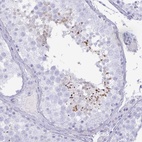

Immunohistochemical staining of human testis shows moderate cytoplasmic positivity in spermatids.